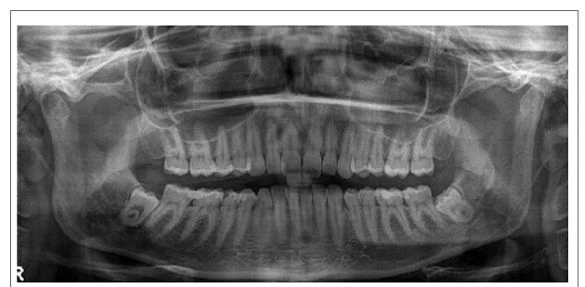

Микропротезирование зубов представляет собой один из способов устранения дефекта, образование которого вызвано различными причинами. Это реставрация целостности зуба с помощью микропротеза, изготавливаемого индивидуально для каждого пациента. Методика является щадящей, т.к. сводит к минимуму воздействие на мягкие и твердые ткани полости рта, а также сокращается время восстановления разрушенной зубной единицы.

Методика применяется при невозможности сохранения эстетики с помощью пломбирования. При этом установка протезной конструкции нецелесообразна.

Особенностью микропротезирования является сохранение зубных единиц, эстетику которых уже, казалось бы, невозможно восстановить. Причем, отсутствует необходимость в их препарировании или допускается минимальная обработка. Находящиеся рядом зубы также не подвергаются обтачиванию.

Для реставрации дефективных участков зубов применяются микропротезы, размер которых определяется степенью разрушения единиц. Ортопедические конструкции изготавливают из различных материалов. Среди них: керамика, пластик, композитные материалы, металл.